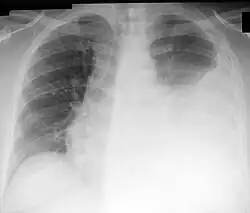

Een pleurapunctie (of thoracentesis) is een invasieve procedure om pleuravocht of lucht bij een pneumothorax te verwijderen, waarbij er verdere diagnostiek naar dit vocht kan plaatsvinden. Hierbij wordt een holle naald tussen de ribben in de pleuraholte gebracht, waarna vocht opgezogen wordt. In het algemeen wordt hierbij geen verdoving gebruikt, omdat dat een extra prik zou vereisen. Deze procedure werd voor het eerst beschreven in 1852.

Deze procedure is noodzakelijk indien zich onverklaard pleuravocht ophoopt in de borstholte tussen de longvliezen. Als zich veel pleuravocht ophoopt kan deze procedure ook plaatsvinden om tegelijkertijd het pleuravocht te laten aflopen. Hierbij wordt een drain achtergelaten in de pleuraholte.

De belangrijkste complicaties van een pleurapunctie zijn het ontstaan van een pneumothorax en een hematothorax. Zeldzaam is het ontstaan van re-expansie oedeem na het verwijderen van grote hoeveelheden pleuravocht.